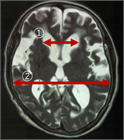

1. 頭部画像所見では、脳室拡大所見とともに

1. 不均衡に拡⼤したクモ膜下腔(脳溝)所見であるDESH(Disproportionately Enlarged Subarachnoid Space)所見

1. 拡大したシルビウス裂所見、高位円蓋部脳溝の狭小化所見、急峻な脳梁角所見などに注目する。

1. 画像診断上、DESH所見、脳梁角の急峻化所見が、iNPHの診断、手術効果予測に有用である。